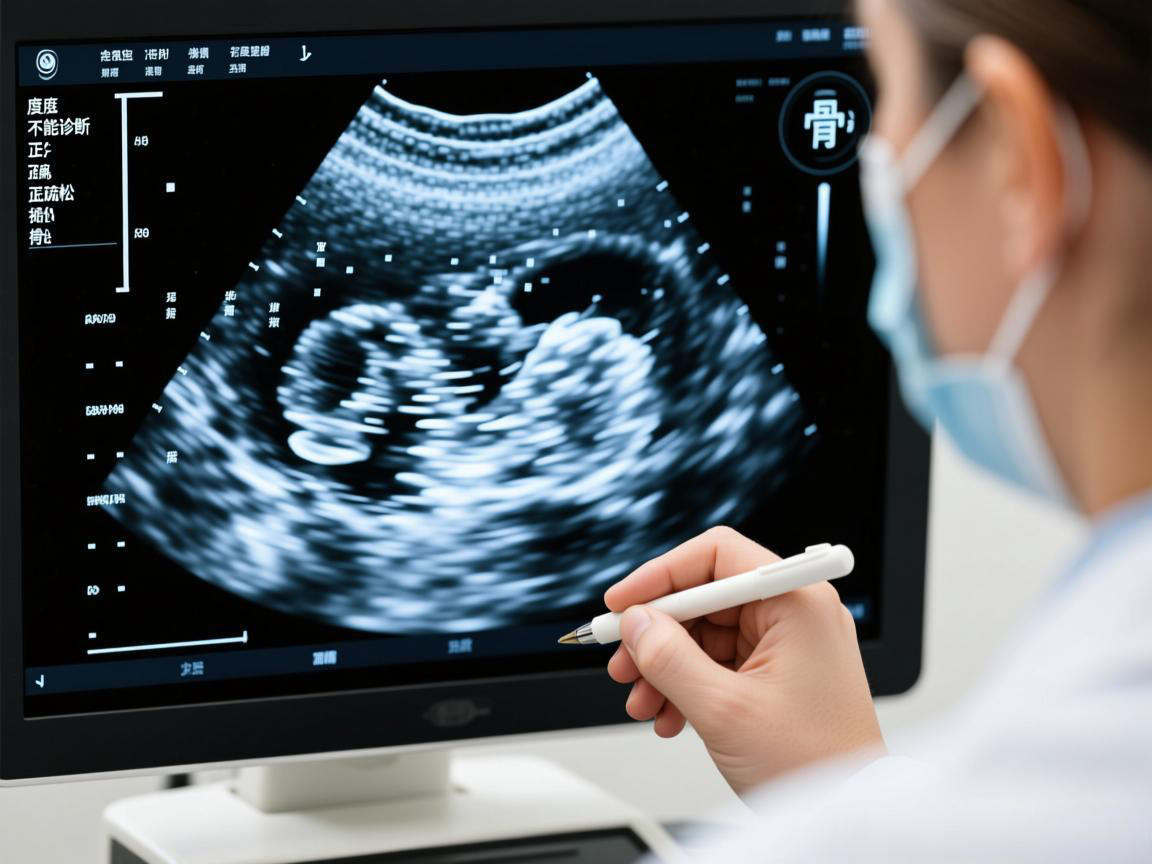

B超骨密度不能诊断骨质疏松!正确方法揭秘

部分中老年人使用B超检测手腕和脚后跟骨密度来诊断骨质疏松是不准确的。建议通过双能X线吸收法(DXA)或定量CT(QCT)进行检测以明确诊断。